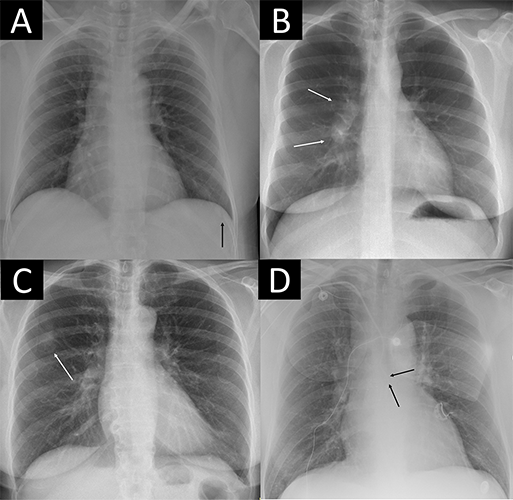

Four examples of remarkable chest X-rays with missed critical findings. The artificial intelligence (AI) tool was postprocessed by the AI vendor by scaling each of the 85 remarkable individual predictions to a normalized value and using the case-level highest of the scaled scores as the overall probability score from 0 to 1 for “remarkableness” (ie, the probability for abnormal or remarkable findings by the AI). (A) Chest X-ray in a 49-year-old female patient shows a slightly visible acute rib fracture (arrow) that was missed by the AI at all thresholds and also missed by the radiology report. (B) Chest X-ray in a 30-year-old female patient shows enlarged hilar lymph nodes (arrows) missed by the radiology report but not the AI at any threshold. (C) Chest X-ray in a 67-year-old female patient shows a tumor mimicking pleural plaque (arrow) that was reported in the radiology report (where the patient was referred for CT) and missed by the AI at the 98.0% threshold but not the 99.0% and 99.9% thresholds. (D) Chest X-ray in a 64-year-old male patient shows a central venous catheter possibly entering the azygos vein (arrows), which was classified as unremarkable in the radiology report. The AI missed the critical finding at the 98.0% threshold but not the 99.0% and 99.9% thresholds.